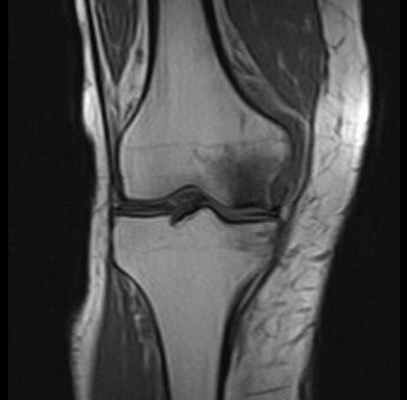

МРТ при некрозе костей колена. Нормальная ширина суставной щели, суставный хрящ ещё не поврежден. Отчетливое изображение некроза внутреннего мыщелка бедренной кости. © Prof. Dr. med. Sven Ostermeier

При недостаточном кровоснабжении костей погибают отдельные костные клетки. Таким образом некроз кости (Болезнь Альбека) означает потерю костного вещества в коленном суставе. Другими словами, остеонекроз — это отмирание костных структур.

- 1-ая стадия: на этом этапе возникают самые сильные боли, которые могут продолжаться от 6 до 8 недель. Рентген без изменений, МРТ или сцинтиграфия костей скелета могут доказать наличие некроза.

На ранней стадии Болезнь Альбека можно диагностировать при помощи магнитно-резонансной томографии МРТ, которая показывает характерную, болезненную отечность. Измерение плотности костей необходимо для исключения остеопороза всей костной системы человека.